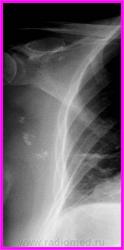

Внелегочные обызествления. Набор изображений.

Различного размера обызествления подмышечных л\узлов, которые иногда, могут симулировать легочные образования (сумация теней, неправильная укладка и т.п. ....